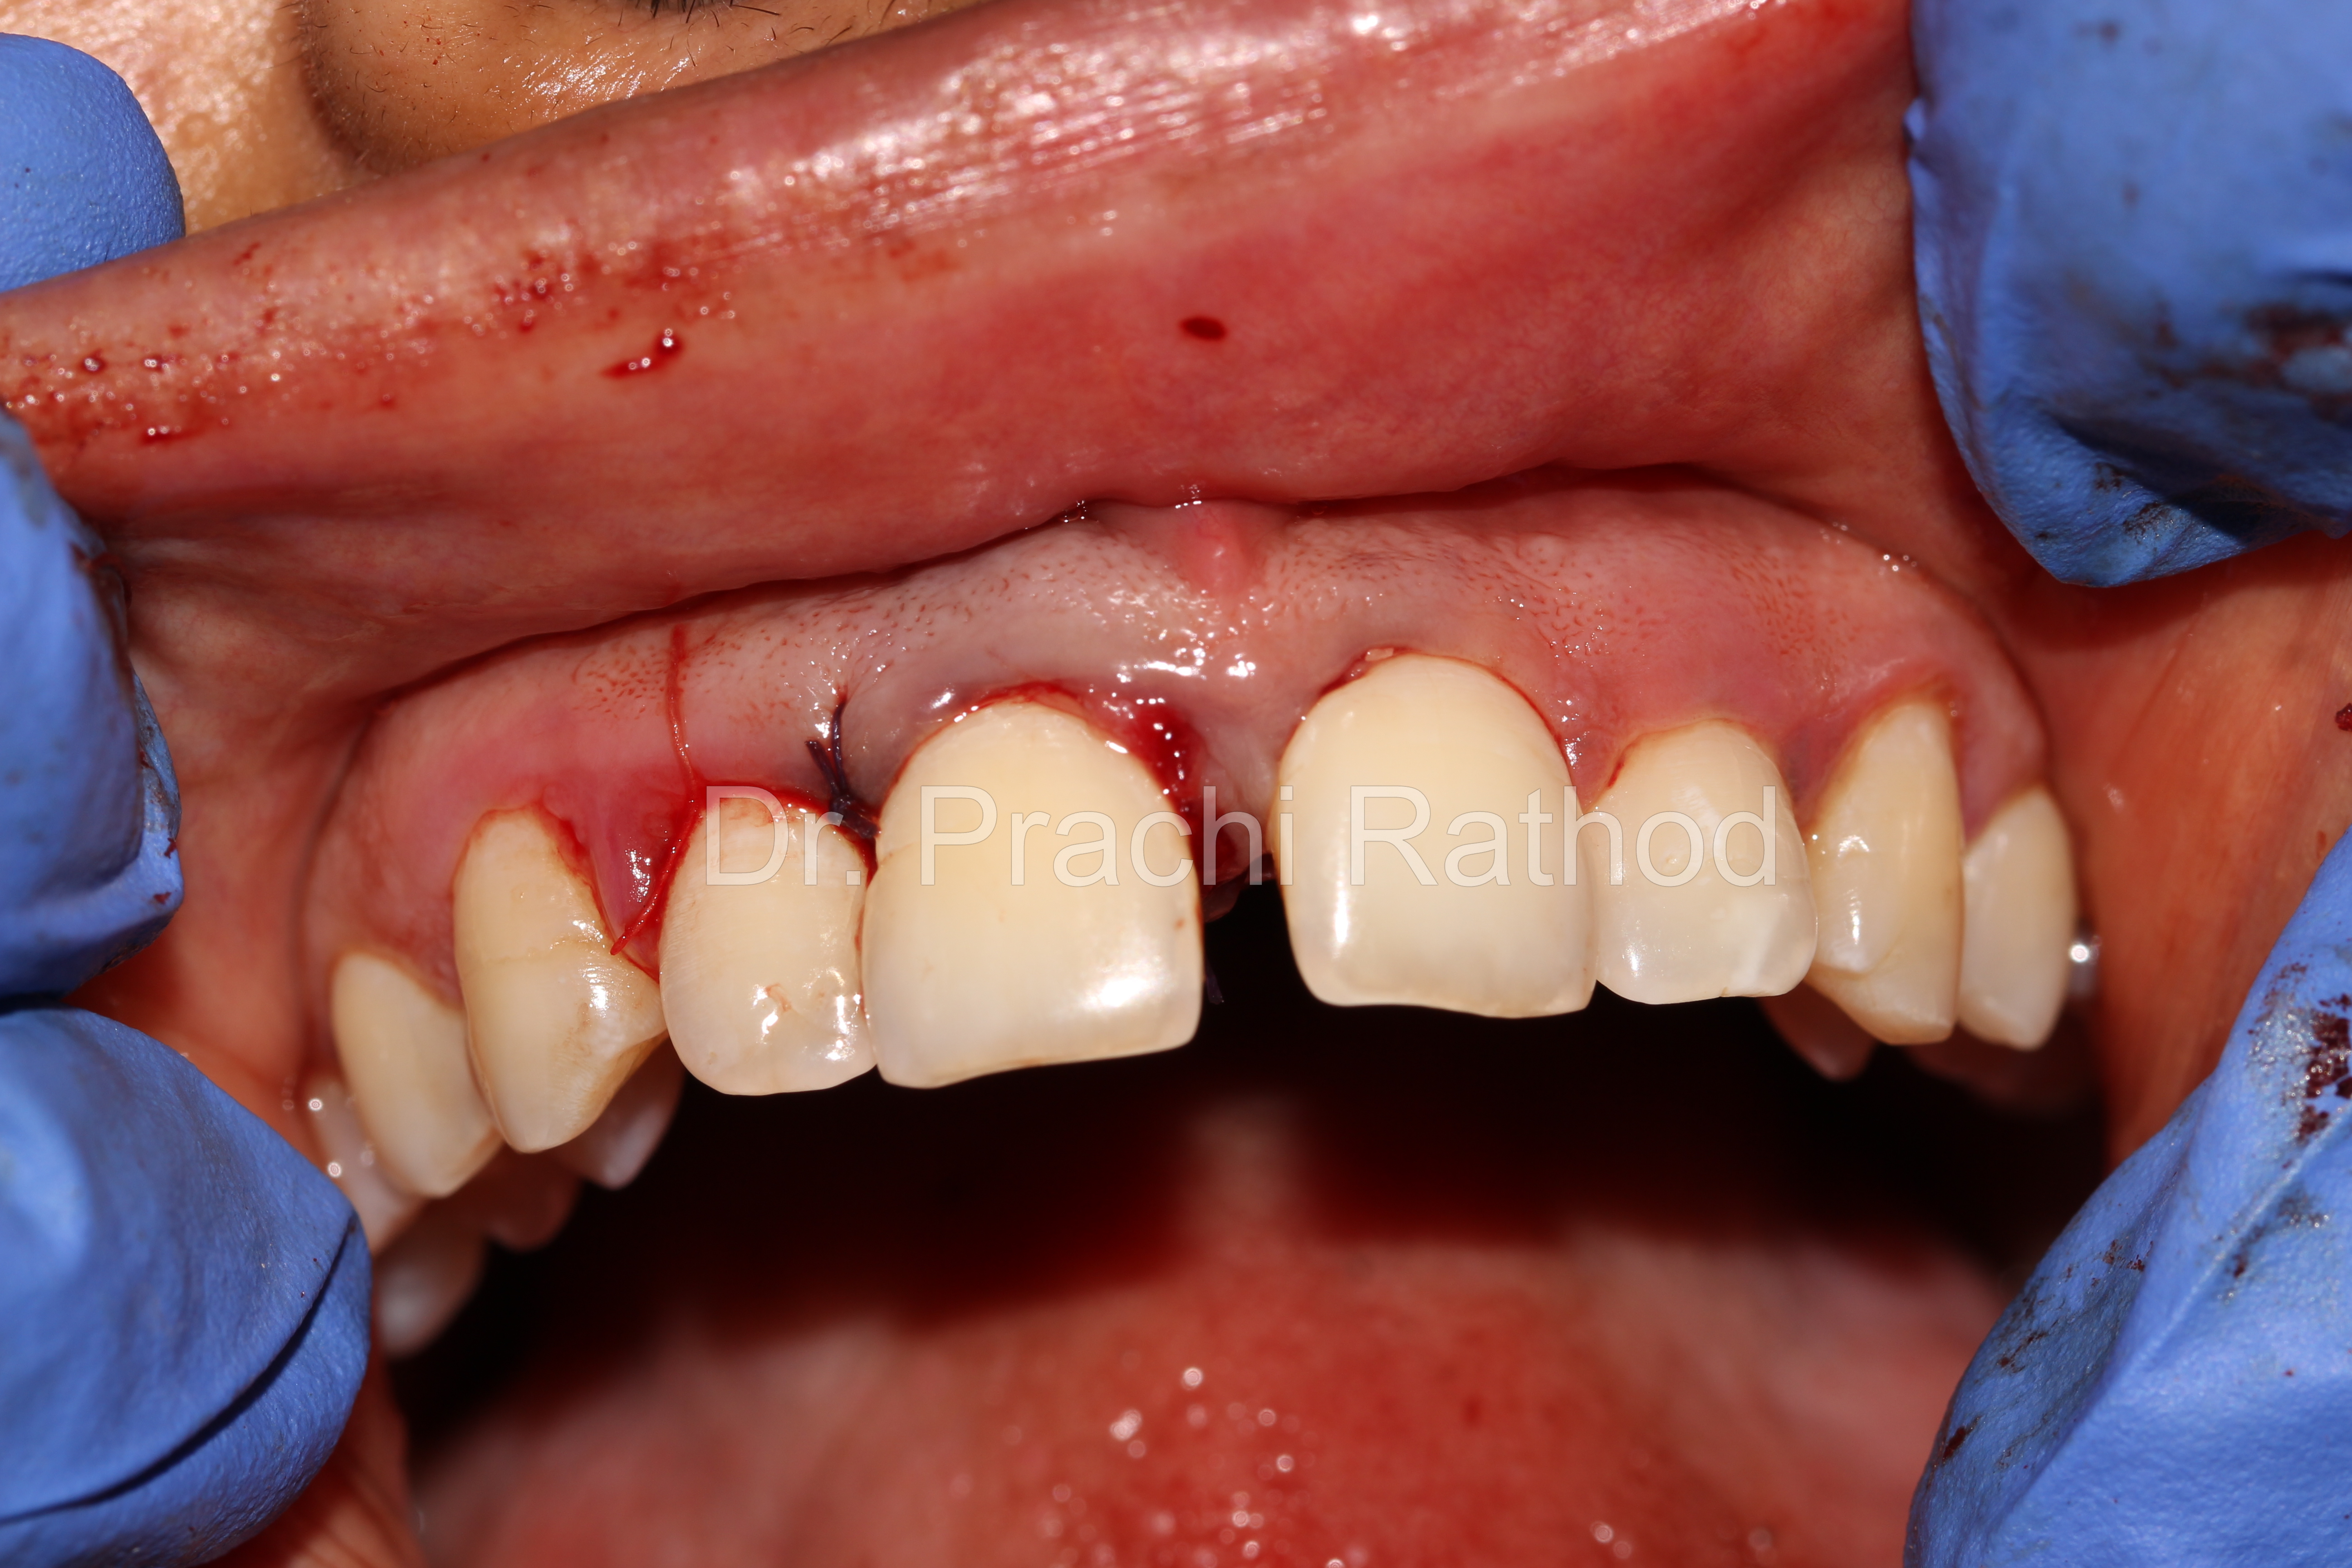

Suturing